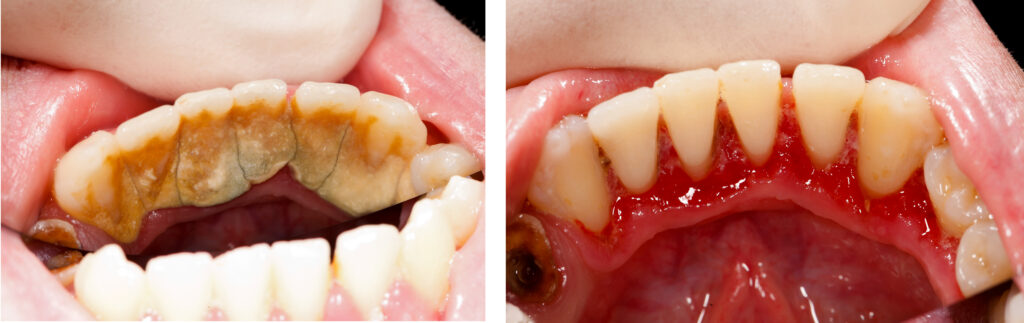

Teeth Cleaning and Gum Care

Even with daily brushing and flossing, plaque and tartar can build up in hard-to-reach areas. Over time, this buildup can lead to:

Professional dental cleaning removes hardened tartar and bacteria that regular brushing simply can’t eliminate.

Gum Care & Periodontal Health

Healthy gums are just as important as healthy teeth.

If left untreated, gum disease can progress from mild gingivitis to more serious periodontitis — potentially leading to tooth loss.